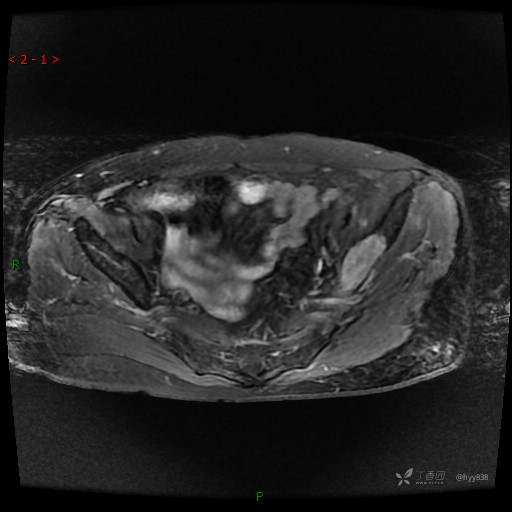

MRI T1WI+T2WI axi

Cor T1WI T2WI -fs